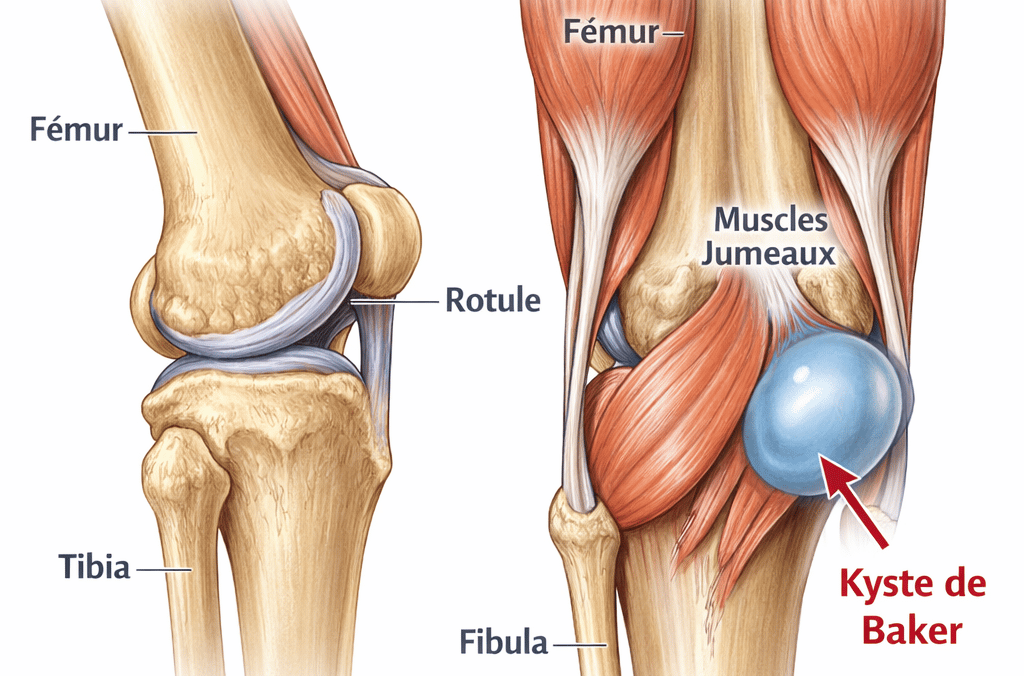

Kyste de Baker

Le kyste de Baker est l’une des causes les plus fréquentes de douleur derrière le genou.

Il correspond à une accumulation de liquide articulaire dans le creux poplité.

Les symptômes peuvent inclure :

gonflement derrière le genou

sensation de tension

douleur lors de la flexion du genou